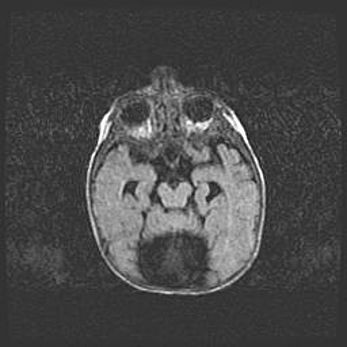

Наружная гидроцефалия с возможной атрофией височных областей.

Возраст: 28 дней

Вес: 3670 г

Пол: мужской

Окружность головы: 38 см

Срок гестации: 40 недель

Гидроцефалия головного мозга у новорожденных – это заболевание, которое характеризуется скоплением избыточного количества спинномозговой жидкости в желудочковой системе головного мозга в результате затруднения её перемещения от места выработки к месту поглощения в кровеносную систему или вследствие нарушения абсорбции. При открытой наружной форме гидроцефалии у новорожденных расширяются и переполняются субарахноидные пространства.

При нормотензивных  формах,  которые,  как  правило,  являются  следствием  перенесенных ишемических  повреждений  паренхимы  мозга,  возможно  сочетание микроцефалии  с нормотензивной гидроцефалией. В основе данных изменений лежит атрофия больших полушарий с преимущественной  локализацией  в  лобно-височных  областях.